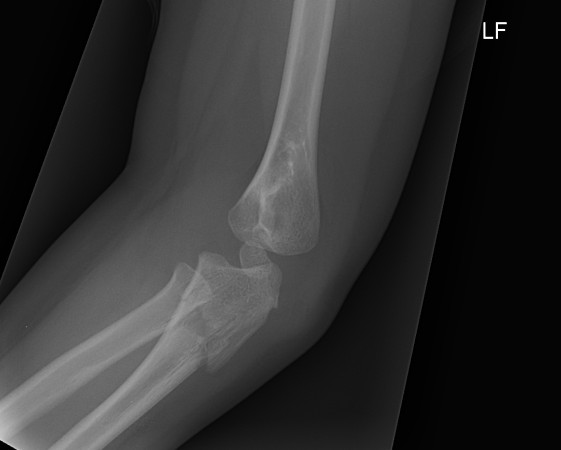

Monteggia

Definition

Fracture / plastic malformation of proximal ulna with dislocation of radial head

Xray

Radio-capitellar line disrupted